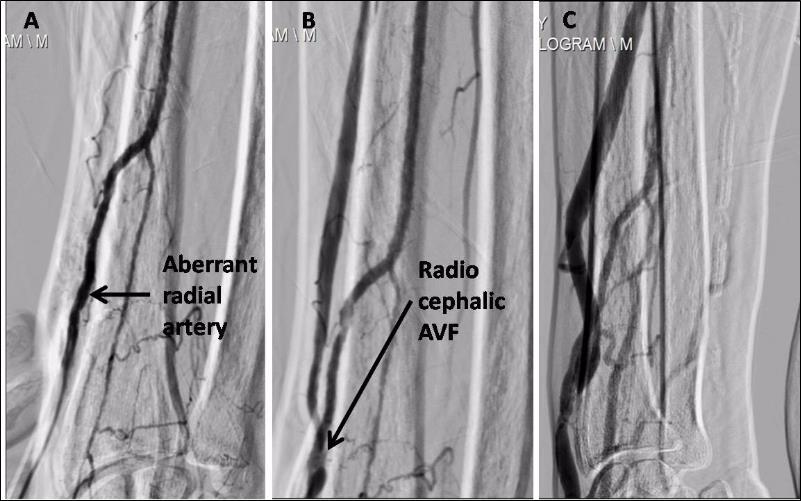

A 75 year male, known case of diabetes mellitus type 2 and hypertensionwas recently detected to have chronic kidney disease requiring hemodialysis. He was considered for arteriovenous fistula (AVF) as a long term vascular access. He was found to have bilateral anomalous radial artery. The encountered vessel coursed abnormally superficial to the tendons of the extensor pollicus brevis (EPB), abductor pollicus longus (APL) and extensor pollicus longus (EPL) lying lateral to the cephalic vein as it passed through the anatomical snuffbox. A right radiocephalic AVF was constructed with side to side anastomosis (Figure 1). AVF angiogram demonstrated an aberrant course of radial artery with well developed AVF (Figure 2). Patient is successfully undergoing hemodialysis through the same fistula since 1 year. To best of our knowledge, this is the first case of AVF with aberrant radial artery to be reported in world literature.

Figure 2.A. Aberrant course of right radial artery. It normally lies above the lateral epicondyle of radius bone, fistulogram demonstrated its course away from radius bone. B. Working right radiocephalic AV Fistula. Right cephalic vein is seen medial to the artery at the site of anastomosis and later running lateral to it. C. A well developed cephalic vein suitable for cannulation for hemodialysis.